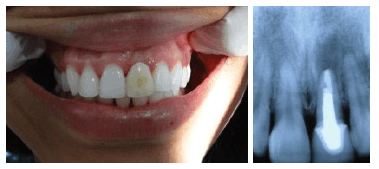

Exemplos Implantes Imediatos

Reabilitação Unitária

Resultado Imediato